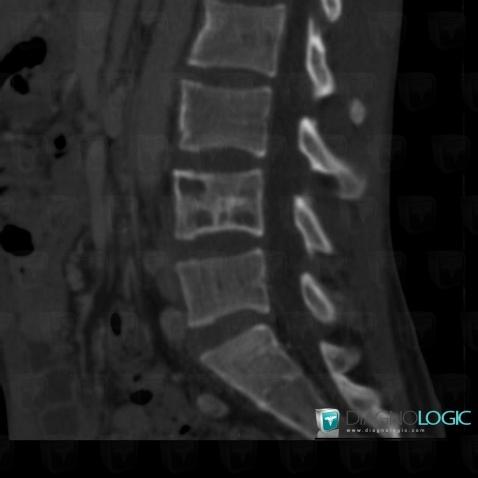

Tuberculosis, Soft tissues - Head and neck, Paraspinal, Theoretical

Here is the specific information in the key image above:

- Diagnosis Tuberculosis (link to Osteomyelitis), Location(s) Soft tissues - Head and neck, with gamuts Paraspinal soft tissue massParaspinal, with gamuts Paraspinal soft tissue mass